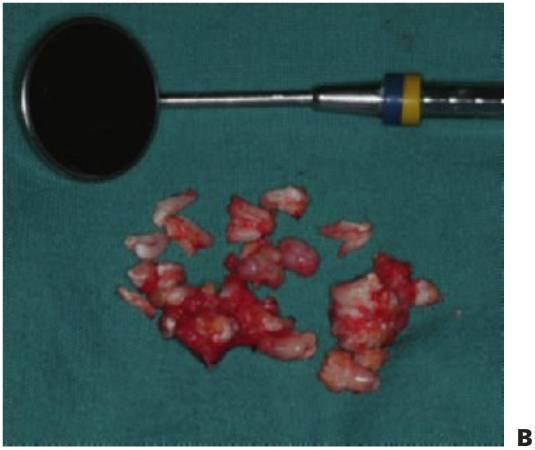

Odontomas

Los odontomas se producen debido a una alteración de la diferenciación, y suelen presentarse debido a la falta de erupción de un diente permanente. En los odontomas compuestos se encuentran masas de dentículos irregulares en un estroma de tejido blando circunscrito. Los odontomas complejos son alteraciones de tipo desorganizado, con una masa aislada e incidental de tejido calcificado que contiene todos los elementos dentales. Un diente de la serie normal puede sustituirse por un complemento dental normal o bien por un odontoma (fig. 9.12).

Tratamiento

- Enucleación.

- Dependiendo de la duración del diagnóstico, los dientes permanentes pueden quedar en una posición ectópica y pueden requerir exposición quirúrgica y alineación ortodóncica.